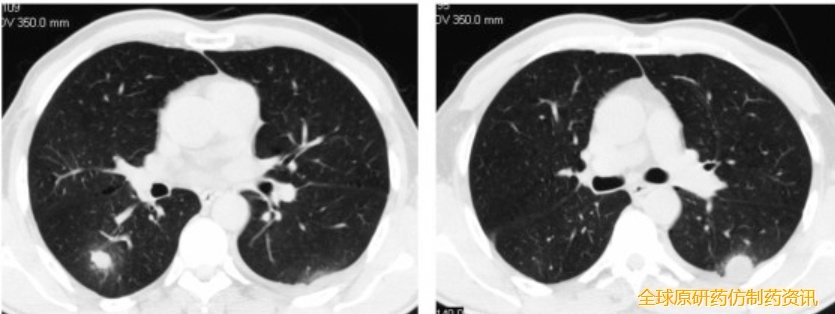

4周化疗后双肺后部肿块完全消失,随后接受肺癌疫苗治疗,持续完全缓解长达8年

这位幸运的患者既往接受三线化疗和放疗均失败,但在使用 Neo-DCVac 后 7.6 个月内未出现任何疾病进展迹象。在五剂个性化Neo -DCVac 免疫治疗之前和之后进行 CT 扫描显示肿瘤靶病灶显著消退。